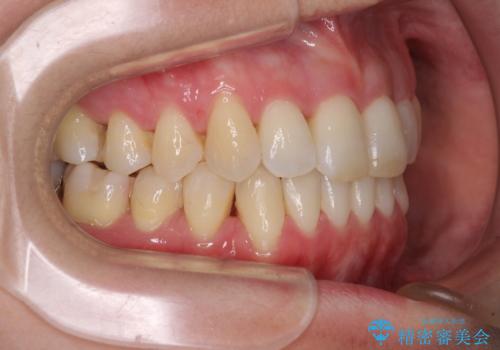

- 奥歯の咬み合わせを気にして来院された患者様です。

上顎骨の幅が下顎骨よりも小さいので、拡大装置により骨幅を広げて上下関係を改善し、その後インビザラインにて歯並びを整えることとしました。

上下の骨幅を改善したことで、スムーズに歯列矯正を行うことができました。

奥歯の咬み合わせを改善する必要があったため、治療は長期化しましたが、きっちりと仕上げることができました。